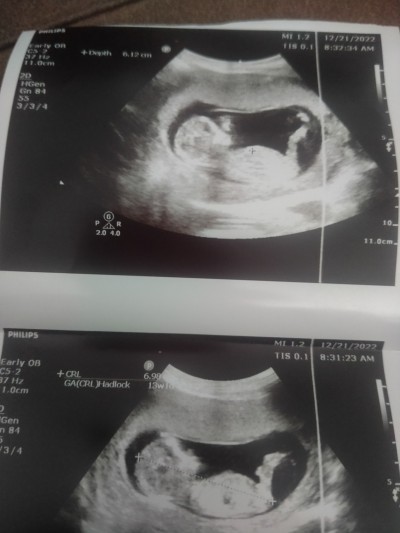

sizce cinsiyet tahmini olan varmı annelerim.cevabiniz için şimdiden teşekkürler hayırlı akşamlar ♥️

Kız bebiş bu kemik yapısına göre.  Doktorunuz tahminde bulunmadi mı

Canım benim bakar bakmaz direkt içimden erkek geçti benim oğlumun da aynen bu şekilde var ultrasyon resmi sanki aynısı gibi kız Allah analı babalı büyütsün sağ sağlıklı kucağına almayı nasip etsin :) ❤️